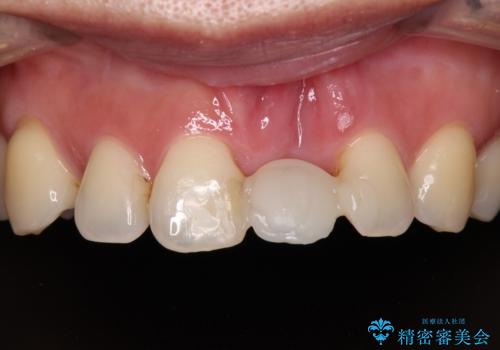

中途半端な矯正治療と前歯の欠損 再矯正とオールセラミッククラウンによる補綴治療

矯正治療により前歯横幅のバランスを整えた後に、上顎前歯をオールセラミックブリッジにて補綴治療を行うこととしました。